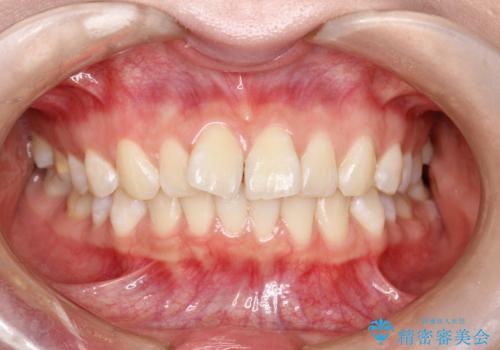

【非抜歯】インビザラインで正しい噛み合わせを